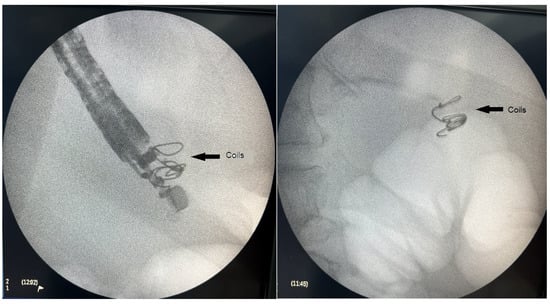

Figure 1, Figure 2 and Figure 3 present post-procedural endoscopic, endosonographic, and fluoroscopic findings.

Figure 3.

Fluoroscopic image of the introduced embolization coils.

Once an adequate position was achieved sonographically, the varix was punctured with a 19 Ga fine needle aspiration (FNA) needle (ExpectTM needle; Boston Scientific, Marlborough, MA, USA). As anticipated, a transgastric approach was associated with a more angulated position of the tip of the endoscope, leading to a more difficult puncture of the target vessel and insertion of the coils. Blood was aspirated to verify an adequate position, followed by rinsing the needle with 4 mL of 5% glucose solution. Next, two 0.035 inch 14 mm/7 cm embolization coils (Nester Embolization coil; Cook Medical, Bloomington, IN, USA) were introduced into the varix. The technique consisted of inserting the coils into the FNA needle, and then pushing them out into the varix using a needle stylet. The procedure was executed under combined ultrasound and fluoroscopic guidance using Philips BV Pulsera C-arm (Philips, Best, The Netherlands). Although primarily used as a scaffold for subsequent glue injection, an immediate reduction of blood flow in the varix was observed upon coil deployment.

The standard approach to coil introduction involves positioning the puncture needle at a distance from the opposite wall of the vessel to reduce perforation risk [26]. The diameter of the coils should be 20–30% larger than the diameter of the vessel to preclude migration [26]. We followed those recommendations with the largest diameter of the varix being 10 mm. We also used two 14 mm/7 cm 0.035″ embolization coils.